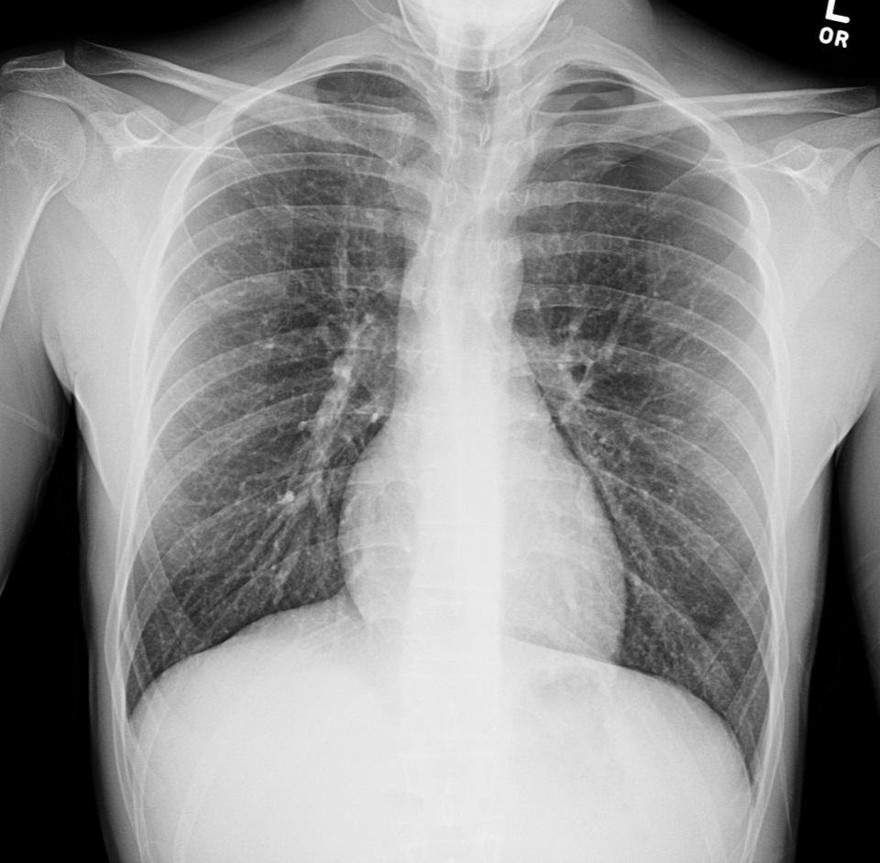

What is the most accurate description of this chest x-ray?

a) Left pneumothorax

b) Normal chest x-ray

c) Covid pneumonitis

d) Right lower lobe pneumonia

e) Congestive heart failure

A